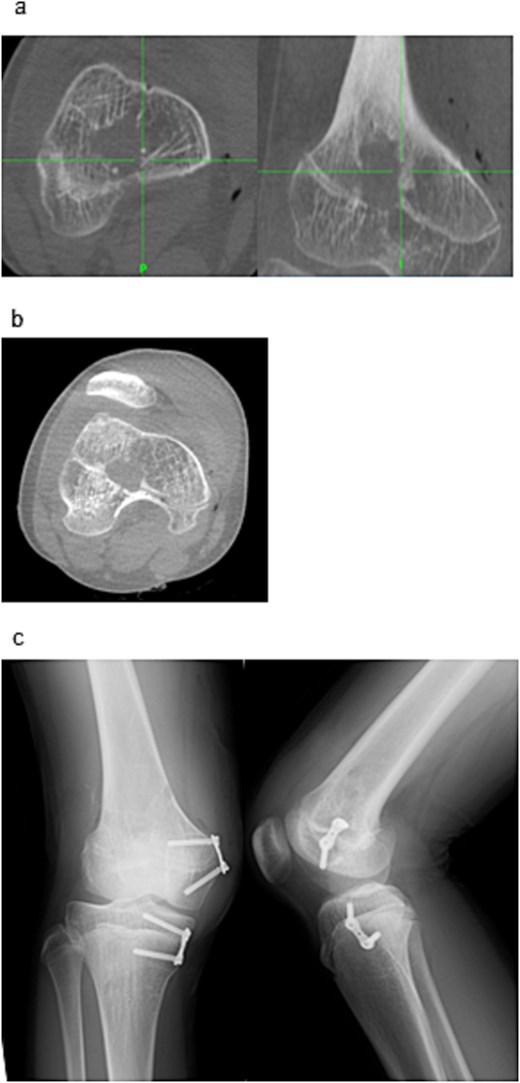

To correct the valgus deformity, an eight-plate (MC Medical Corporation, Tokyo, Japan) was inserted, across the distal medial femur and proximal medial tibia (Fig. 4c). Mild thigh swelling from the irrigation fluid occurred postoperatively; with no signs of compartment syndrome or wound complications. Weight-bearing began the next day with crutch-assisted ambulation guided by pain tolerance. He was discharged on postoperative Day 6, ambulating independently with crutches. At the 24-month follow-up, he reported no pain and improved right knee range of motion (0–140°) (Fig. 5a–c). Radiography showed that the FTA had improved to 168°.

Radiographic findings at 24-month follow-up. (a) Anteroposterior radiograph of the right knee. (b) Lateral radiograph of the right knee. (c) Full-length standing anteroposterior radiograph of the lower extremities.